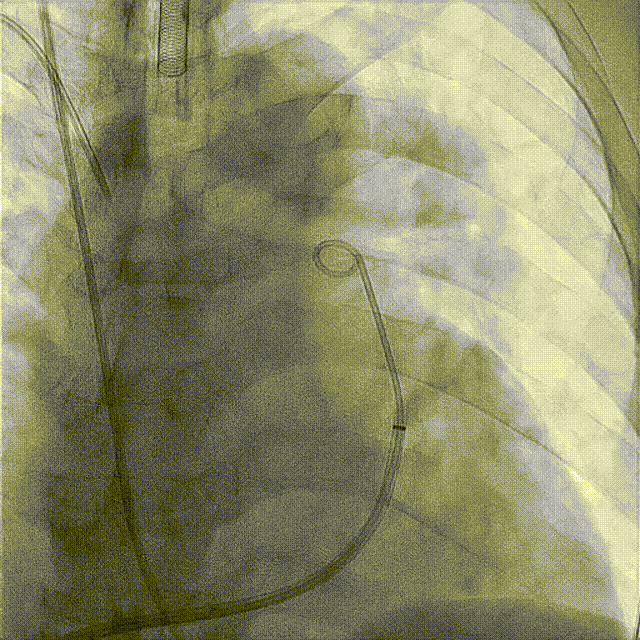

PADN术中造影和导管消融图(见下图):

LAO0°+CRA20°和 LAO20°+CRA20°体位造影

LAO0°+CRA20°工作体位依次进行A、B、C点消融